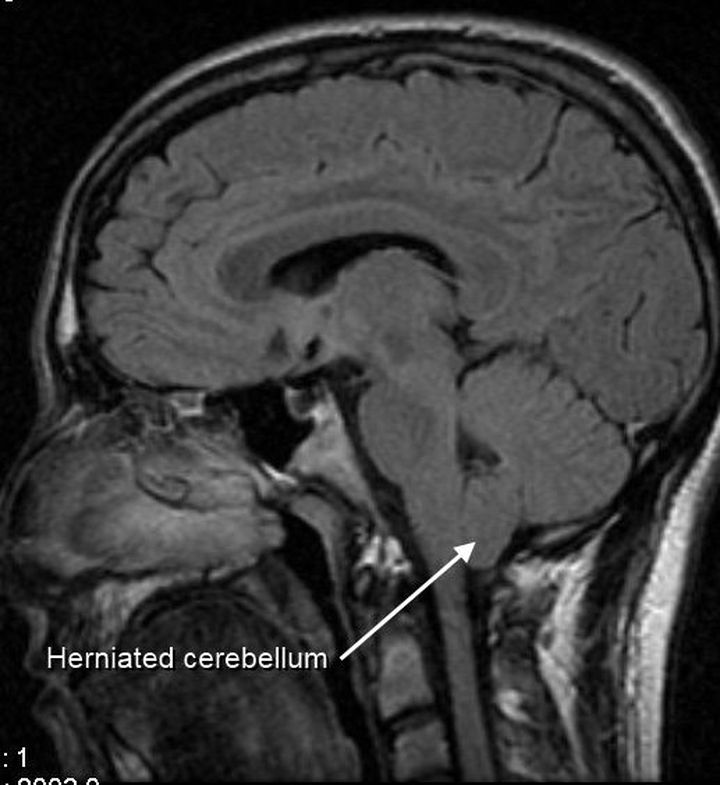

Arnold Chiari malformation

Type 1